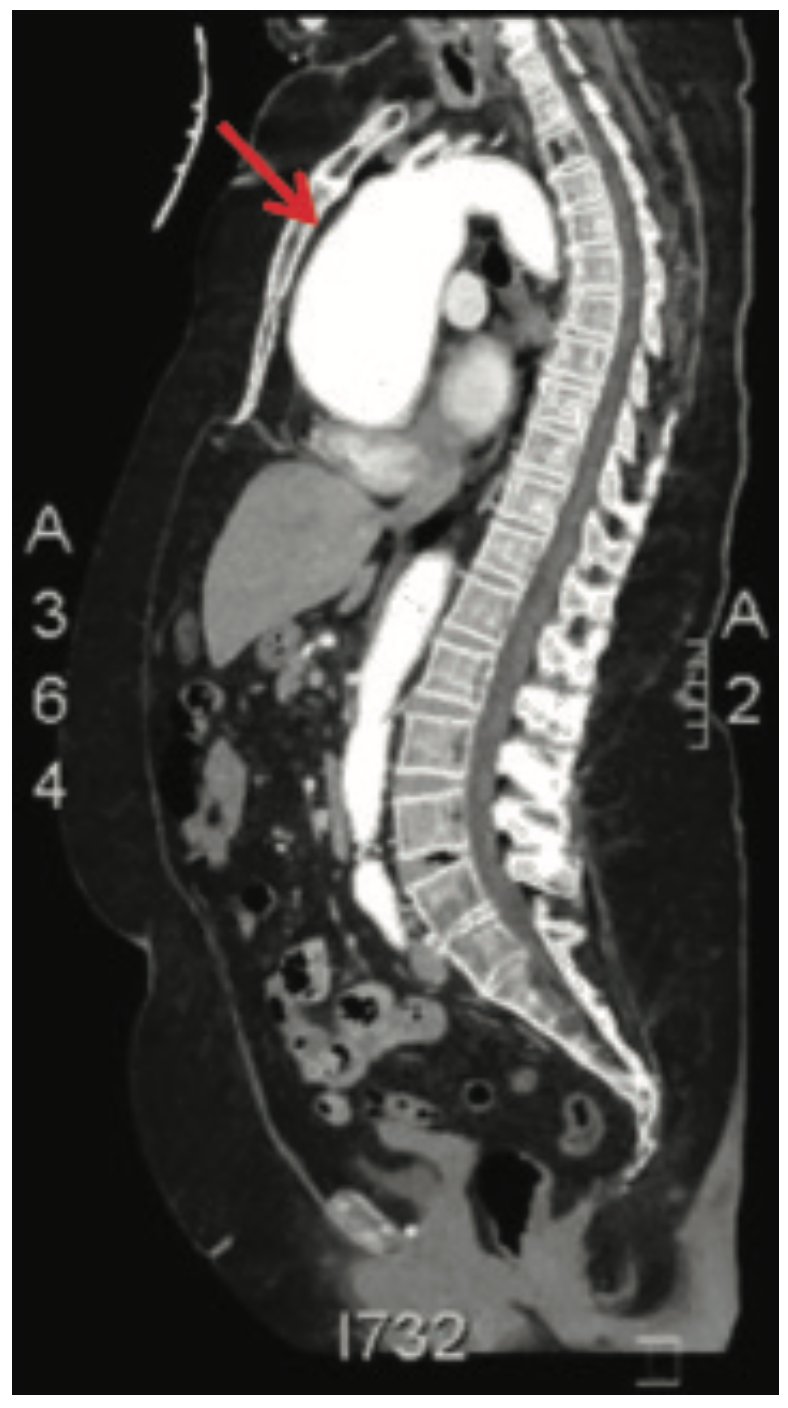

She was widowed, lived alone, and quit smoking 4 years ago, with a 40 pack-year smoking history. Her family history was non-contributory. She had noticed some dyspnea on exertion during routine chores such as mowing the lawn and carrying laundry upstairs, which she attributed to deconditioning. She was otherwise asymptomatic, even during her episode of supraventricular tachycardia (SVT) during her recent colonoscopy. During her TTE, the technologist notified the cardiologist of a 9-centimeter ascending aortic aneurysm, effacing the sinotubular junction with dilated sinuses of Valsalva. The TTE also demonstrated moderate aortic regurgitation. There was no evidence of vegetation or aortic dissection, or pericardial effusion. The patient was admitted to the University Hospital from the office for further management. A computed tomography scan of the chest with contrast was done in the emergency department to further define the aneurysm. Cardiac catheterization was performed the following day, revealing normal coronaries, normal left ventricular systolic function, and a 9-centimeter ascending aortic aneurysm. She underwent urgent cardiothoracic surgery. The surgeon repaired her aortic root with a Dacron patch and replaced her aortic valve with a bioprosthetic pericardial aortic valve. The patient had an otherwise unremarkable post-operative course, primarily consisting of blood pressure control. She was discharged with surgical follow-up within 1 week and cardiology follow-up in 2 weeks.

The diagnosis of a TAA relies on aortic imaging for detection. Aortic imaging is a priority and should not be delayed for other tests, especially for patients with family history of aortic aneurysms.4 CT or magnetic resonance (MR) angiograms are optimal tests to determine the diameter or any changes to the aneurysm.4